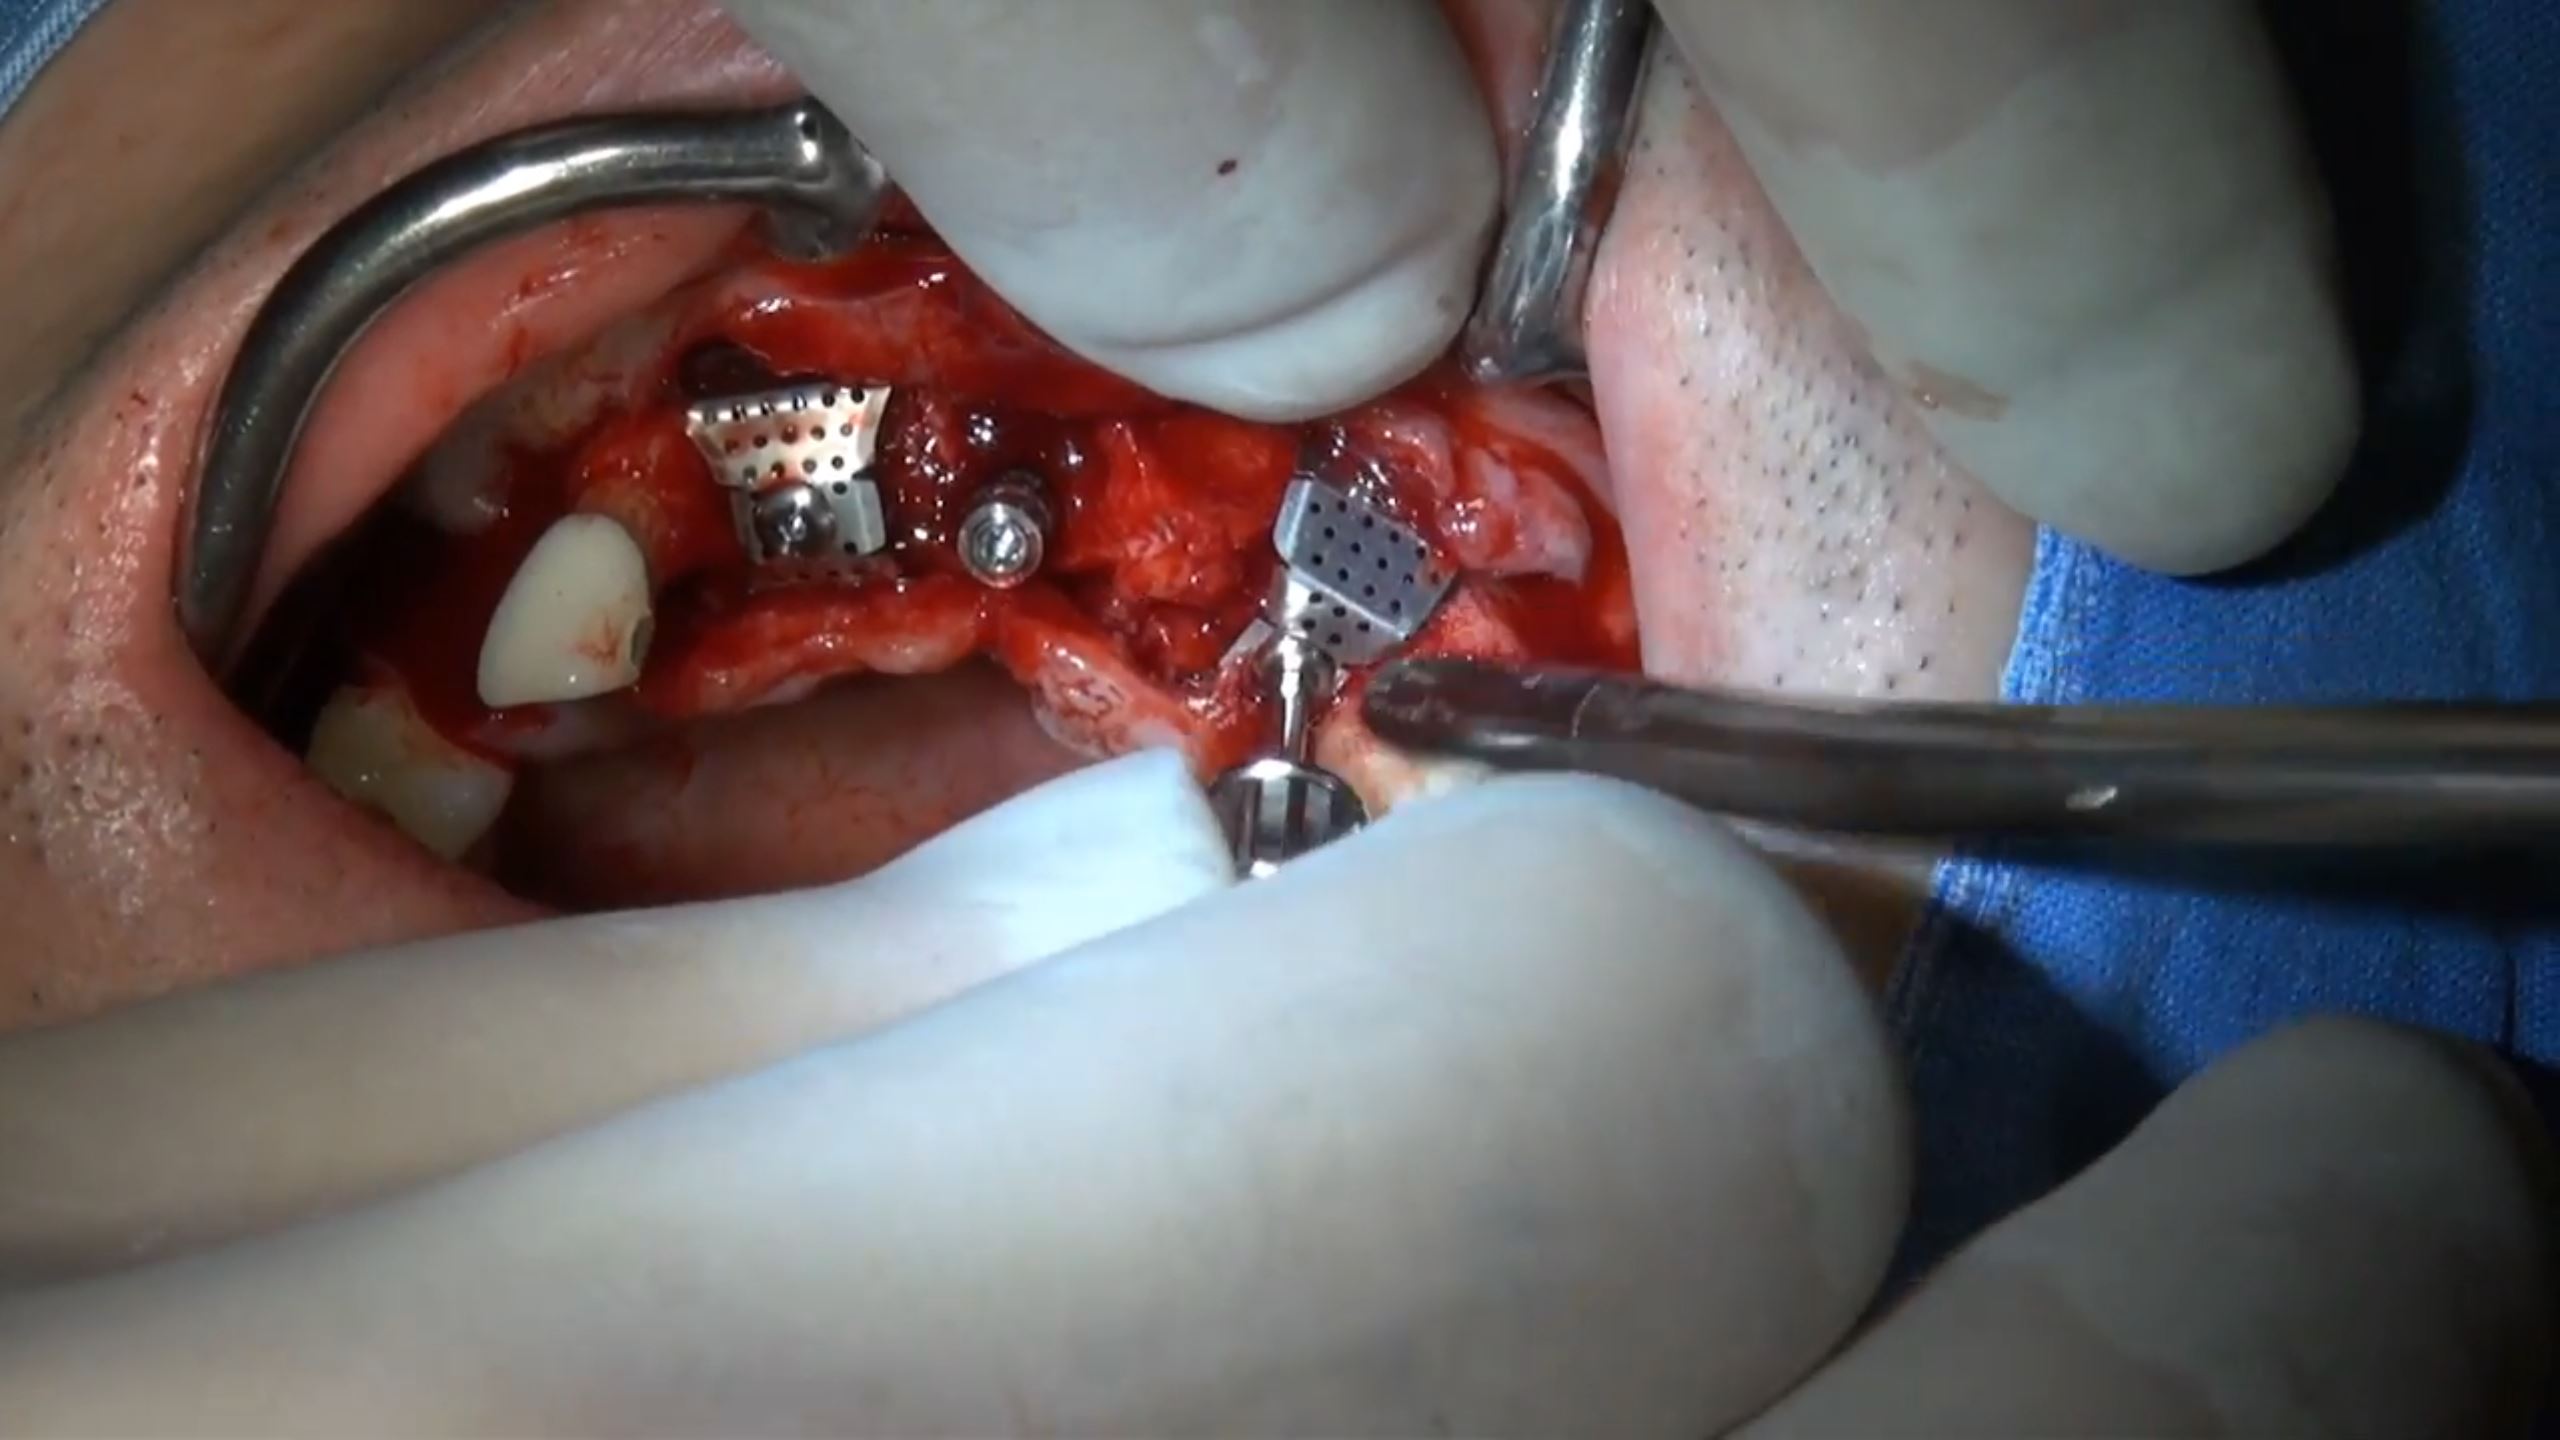

How to get a reliable ISQ!

#23,#24,#25,#26,#27,Aesthetic zone,AnyRidge,Digital,Digital Guided Surgery,Edentulous,Flapless,Immediate loading,Immediate Placement,Maxillary Posterior,MEGA ISQ,R2GATE,R2GATE Guide,R2GATE Surgical Kit(AnyRidge),video